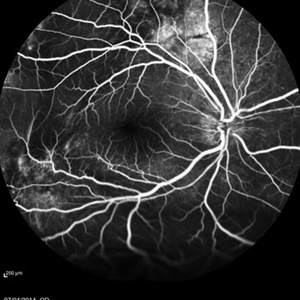

Multifocal Exudative Detachments Due to VKH

May 14 2014 by Avris Romario Diparaja Siahaan

FA a 38-year-old man with multifocal CSR and inferior exudative retinal detachment on both eyes (Harada Syndrome).

Photographer: Avris Romario Diparaja Siahaan, Klinik Mata Nusantara

Imaging device: Heidelberg HRA + OCT Spectralis

Condition/keywords: multifocal central serous chorioretinopathy (CSCR)